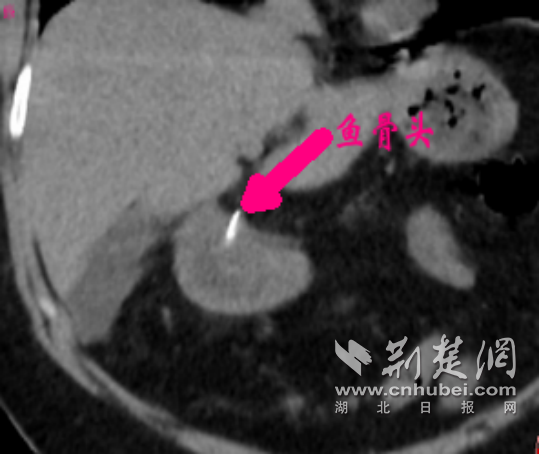

- 中西医结合双镜夹攻巧切“葫芦瘤”